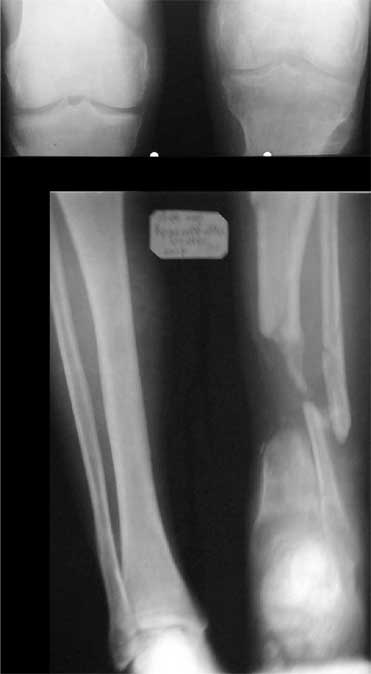

Zdes' snimky posle poslednego montazha apparata prilagaiutsa

Yours Castro

Кликните для загрузки файла IMG_0501.jpg

К сожалению на первичной и последующей рентгенограммах не видно, что творится с голеностопным суставом. Если вилка суства сохранена, то есть смысл побороться за конечность. Интересно, увитеть, что твориться с голеностопным суставом.